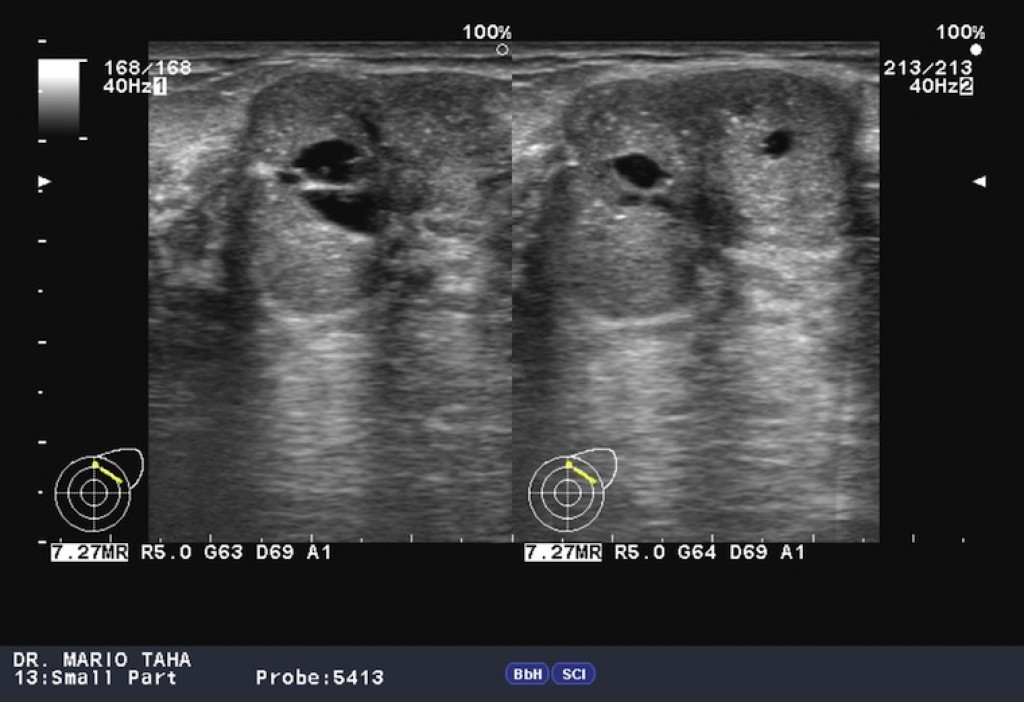

Ultrasound signs of a phyllodes fibroadenoma:

• An iso- or hypoechoic mass;

• Heterogeneous structure, with non-echoic inclusions in the event of large mass size;

• Rounded or oval in shape, with clear, even contours;

• Presence of acoustic effects (symmetrical lateral shadows, dorsal signal amplification);

• Significant intranodular vascularisation in CDI and PD modes;

• Strain-ratio index at elastometry is above 2.5.

A phyllodes breast tumor is shown below on ultrasound images. Author of photos No. 1 and No. 2: Mario Taha. Source: Radiopaedia [10]. Author of photo No. 3: Giorgio M. Baratelli. Source: Radiopaedia [10].